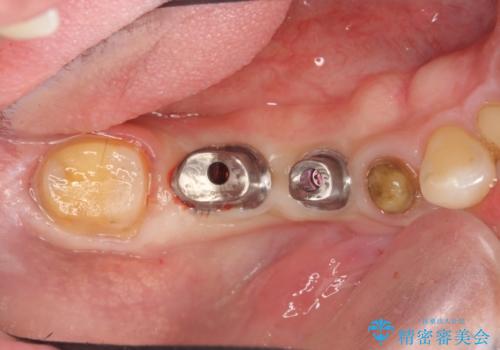

設計に無理のある長期的に良好な状態が保てるとは思えないブリッジを除去し、インプラントを用いた補綴計画を立てます。

- 80万円(ストローマンインプラント×2・チタンカスタムアバットメント×2・ジルコニアクラウン×4)費用は治療当時の料金となります

ブリッジは欠損部位の距離が長くなればなるほど支台となる歯の負担がまし、大きな咬合力負担による外傷や破折など大きなリスクにさらされます。

インプラントを用いることで残っている歯の負担も減らし、長期的な予後を見込むことができます。